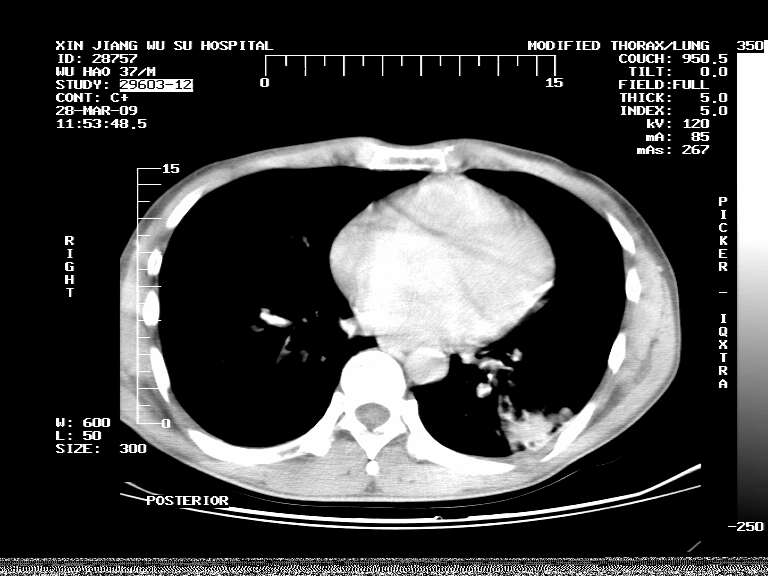

男,37岁,体检胸透发现阴影。

患者体检发现 无症状 左肺下叶占位,边缘模糊,可见血管聚束、分叶、胸膜牵拉,增强呈不均匀性强化。 首先考虑左肺下叶周围型肺癌,建议穿刺活检。

患者体检发现 无症状 左肺下叶占位,边缘模糊,可见血管聚束、分叶、胸膜牵拉,增强呈不均匀性强化。 首先考虑左肺下叶周围型肺癌,建议穿刺活检。支持!

左肺下叶见一结节病变,边缘欠清不光滑,与胸膜粘连且胸膜局限性增厚,注药后呈环形强化,动脉期壁呈明显点环状强化,静脉期壁强化减低,中心密度低无强化,灶周无明显的卫星灶和水肿区(晕征)---考虑周围性肺癌,不除外感染性病变,建议穿刺活检。

左肺下叶软组织病灶,密度较高,内见点状钙化,其周围见子灶,邻近胸膜扁平样增厚.c+病灶强化明显,中心强化弱.诊断:左肺下叶结核瘤.

周围有卫星灶,胸膜反应不明显,病灶中心有坏死。建议先抗结核治疗后,短期复查

左肺下叶大片实变影,内靠胸膜见不规则更高密度结节灶,边缘强化,相邻胸膜增厚,胸膜下脂肪线存在。考虑炎症,结核可能。